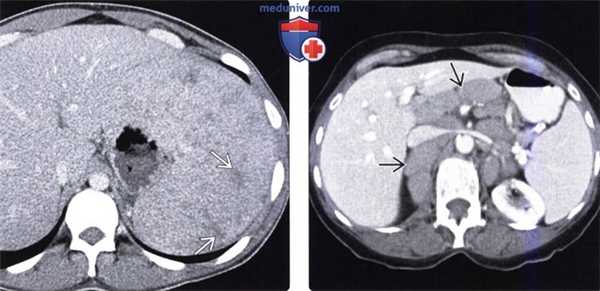

(Слева) На аксиальной КТ с контрастным усилением определяется многокамерное образование в селезенке, которое было верифицировано как пиогенный абсцесс. Такие большие абсцессы нетипичны для селезенки, особенно при отсутствии признаков первичного инфаркта.

(Справа) На аксиальной КТ с контрастным усилением у пациента с недавней травмой селезенки, у которого возник новый виток лихорадки, определяется скопление жидкости (уровень «жидкость-газ») окруженное «ободком», накапливающим контрастное вещество (абсцесс селезенки). Было выполнено чрескожное дренирование абсцесса, пациенту назначены антибиотики. (Слева) На аксиальной КТ с контрастным усилением у пациента со СПИД, обусловленным ВИЧ, с жалобами на снижение веса тела и лихорадку, визуализируются микроабсцессы по всей селезенке. Состояние пациента быстро ухудшилось, и он погиб; при вскрытии были обнаружены множественные туберкулезные абсцессы.

(Слева) На аксиальной КТ с контрастным усилением у наркозависимого пациента 29 лет (вводящего наркотики внутривенно) с жалобами на лихорадку и боль вверху живота слева в течение трех дней, определяется гиподенсный очаг в периферических отделах средней части селезенки (абсцесс).

(Справа) На аксиальной КТ с контрастным усилением у этого же пациента определяются воспалительные изменения около селезенки, которые можно трактовать как разрыв абсцесса. При эхокардиографии были обнаружены многочисленные вегетации на аортальном и митральном клапане, наличие которых позволяет предположить, что абсцесс возник в результате эндокардита.